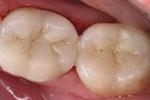

All Porcelain Posterior Crown and Filling

Concerned that their old-fashioned crown and filling were drawing unwanted attention to their smile, this patient requested new, all-porcelain cosmetic work.